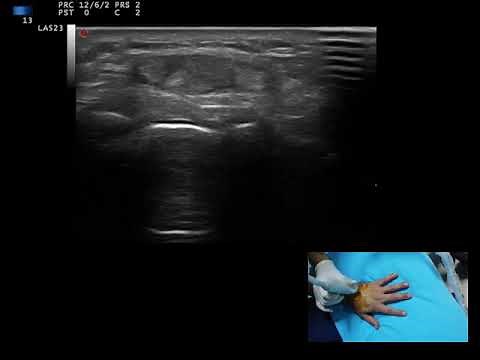

Point-Of-Care Ultrasound for the Diagnosis of Extensor Tenosynovitis - JETem

Point-of-care ultrasound of the dorsal aspect of the left hand reveals a heterogenous hypoechoic fluid collection surrounding the extensor tendons (axial view) within the retinaculum consistent with edema. Longitudinal view shows anechoic fluid within the tenosynovium which is located between the anisotropic extensor tendon and linear ...